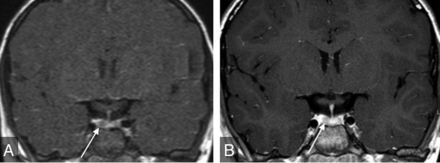

Microadenomas are a common-but-controversial justification for contrast administration in pediatric pituitary MR imaging and are often cited as a reason to include sequences such as dynamic contrast-enhanced images.21 They are seldom clinically relevant without signs and symptoms of hormonal hypersecretion (eg, galactorrhea, hyperprolactinemia). In addition, there are multiple pitfalls associated with imaging diagnosis. First, normally occurring hypoenhancing regions within a heterogeneously enhancing normal pituitary gland may simulate microadenoma (Fig 4). Second, even when a well-delineated lesion is present, functional adenoma cannot be accurately differentiated from nonfunctional adenoma by MR imaging. This finding thus may beget additional lab testing, potentially adding expense, time, and stress to the patient/family experience. Third, if this testing confirms a functional microadenoma, there is still no definitive evidence that the microadenoma is the etiology of the patient’s presenting symptoms. For example, the link between microadenoma and CPP remains controversial, and no relationship between follicle-stimulating hormone–secreting adenoma and CPP has been reported.22 Ultimately, in the setting of GHD, SS, and CPP, the possible microadenoma is usually an incidentaloma.

Coronal dynamic postgadolinium (A) and delayed (B) T1WIs of the sella show heterogeneous enhancement, with hypoenhancement of the right side of the gland (arrows). This finding was considered equivocal for microadenoma, and the patient underwent multiple follow-up examinations despite the finding being considered clinically unrelated to GHD. The finding led to no clinical intervention.